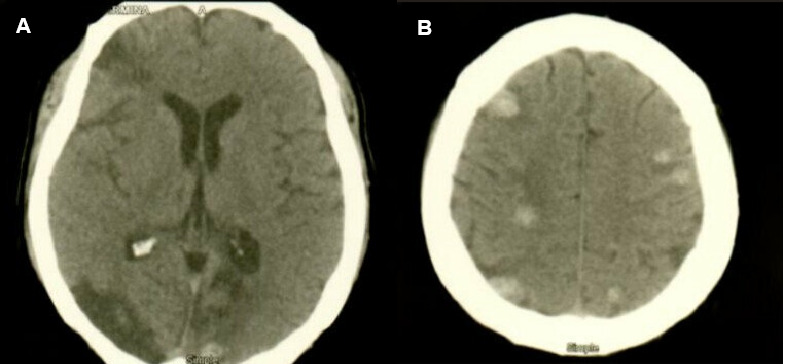

Case presentation: We report the case of a patient with multiple brain metastases, found during follow-up, after the presentation of stroke. This case stands out because the embolization causing the brain metastasis might have occurred either during the ischemic stroke or when the cardiac myxoma was being removed. In our case, the patient was evaluated during follow-up with brain magnetic resonance imaging, finding multiple metastatic lesions. To determine the type of lesion, a biopsy was performed and the histological diagnosis, which was indicative of metastatic tissue of left atrial myxoma.